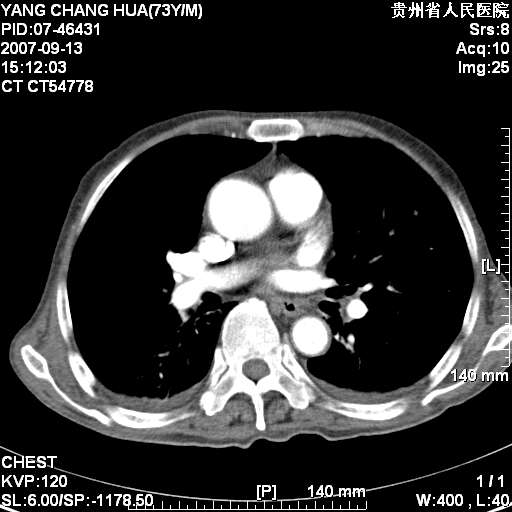

双侧胸腔积液。

肺大泡。

食管癌未除。

双肺散在斑片状及多发小结节状阴影,边缘模糊,双上肺野明显,双侧胸膜腔少量积液,纵隔及肺门区未见明显肿大淋巴结,肝脾肿大,脾内见多发低密度区,结合临床考虑恶性淋巴瘤(肺内表现为肺炎肺泡型),单看影像表现,肺结核不能排除。建议结合实验室检查或表浅淋巴结活检。